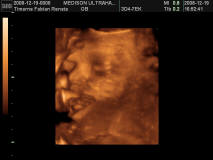

Dávid arcocskája